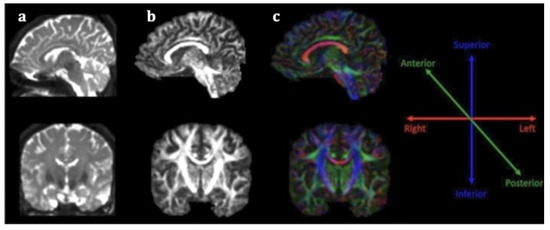

Stroke diagnosis has been facilitated by the incorporation of advanced neuroimaging modalities in clinical practice, especially diffusion weighted imaging (DWI), a technique based on the motion of water molecules. Nevertheless, conventional magnetic resonance imaging (MRI) is incapable of accurately illustrating microstructural impairment on white matter (WM) tracts, rendering its role in predicting stroke outcome limited. Conversely, diffusion tensor imaging (DTI) is an extension of this modality for in vivo mapping of white matter (WM) directionality and organization, allowing the qualitative and quantitative evaluation of major WM tracts and their microstructural integrity [6]. DTI is based on the random diffusion of water molecules [7]. In WM, water diffusion is slower perpendicular to the fibers, but it occurs faster along their longitudinal axis, producing anisotropic diffusion. The extent of anisotropy is influenced by integrity and organization of the WM tract and water diffusion mobility generated by axonal membranes and their myelin sheaths. Different computational algorithms are used to track different WM bundles and study WM organization in healthy participants and different disease samples [8]. The most widely employed DTI parameters are fractional anisotropy (FA), mean diffusivity (MD), axial diffusivity (AD), and radial diffusivity (RD). FA measures the preferential directionality of diffusion and is quantitatively expressed in numerical values between 0 and 1. High FA values indicate a greater degree of preferential directionality (anisotropic diffusion). Such a high degree of preferential directionality is commonly observed in highly organized WM tracts. On the other hand, low FA values indicate less preferential directionality of water molecules (isotropic diffusion). Low FA values close to 0 are observed in gray matter and cerebrospinal fluid. MD indicates the diffusion magnitude, AD describes the diffusivity along the dominant diffusion direction, and RD portrays the average diffusivity of two shorter eigenvectors [7]. It has been suggested that AD is mostly related to axonal degeneration whereas RD is mostly linked to demyelinating processes [9]. DTI offers directional information on water molecule diffusion and provides additional maps, including the fractional anisotropy (FA) map and the color-coded directional map (Figure 1). The color-coded directional maps are based on the convention that the blue color represents the water molecules that diffuse in an inferior–superior direction, the green color represents that water molecules that diffuse in an anteroposterior direction, and the red color represents the water molecules that diffuse in a left–right direction. Although DTI has not yet been incorporated in routine clinical care in stroke, a growing body of research suggests that it is a promising imaging biomarker for stroke recovery, owing to its ability to imprint white matter tract integrity in detail [9].

Figure 1.

Sagittal (first line) and coronal (second line) section of DTI data (a), fractional anisotropy map (b) and color fractional anisotropy map (c). The color-coding of the white matter tracts in the color fractional anisotropy map follows the assumption: red for left–right-oriented fibers, blue for superior–inferior-oriented fibers and green for anteroposterior-oriented fibers.